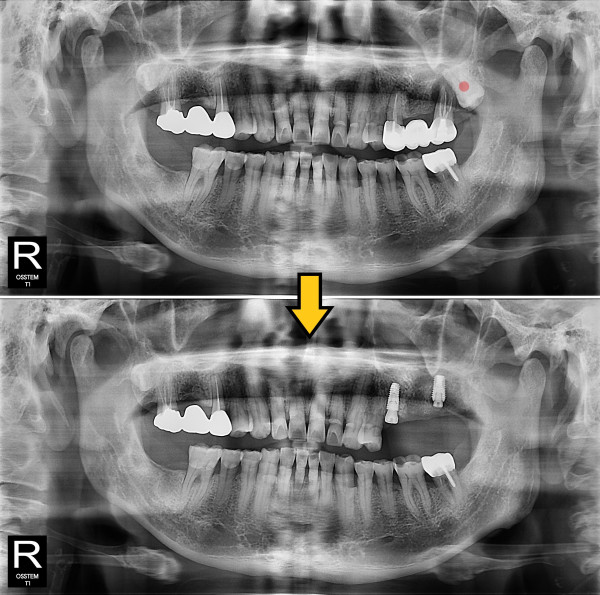

사랑니발치 완전 매복 사랑니

826e40416d712e6cd444a78bde93df4b_1767857243_6817.jpg